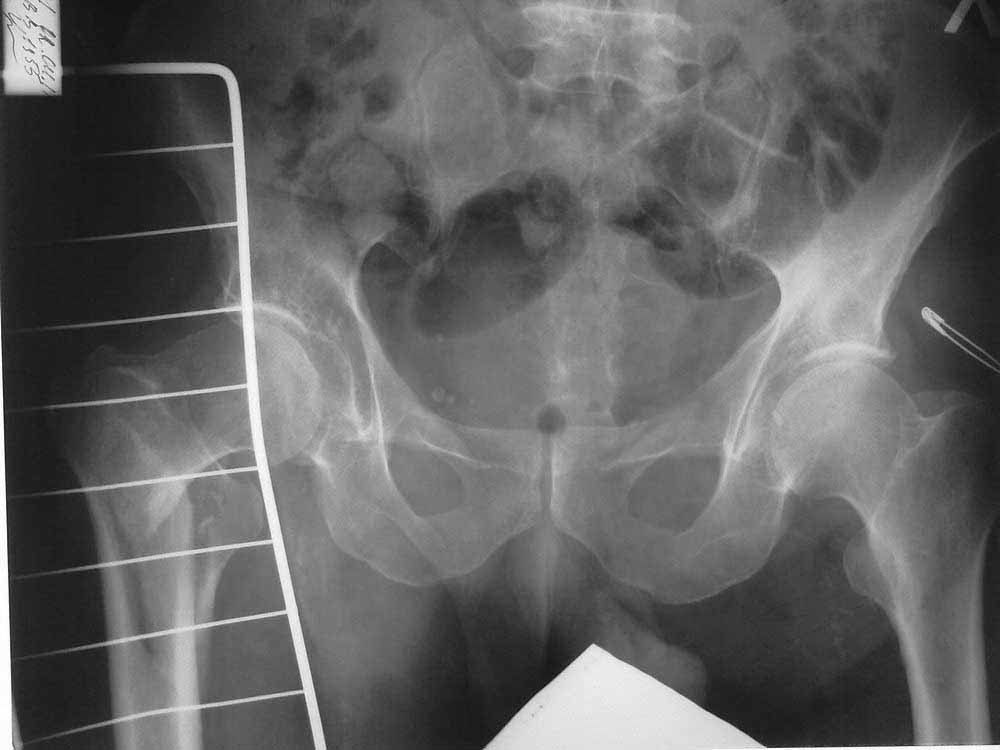

Уважаемые коллеги! Подскажите тактику ведения больного с чрезвертельным перелом.

Больной 56 лет. Травма в быту, упал на правое бедро. Доставлен по линии скорой помощи. Правая нижняя конечность ротирована кнаружи, укорочение на 4 см. Резкая боль в области правого ТБС.

В анамнезе инсульт от 04.2010 г, повторный инсульт 28.02.2011 г. DS:Хроbrническая дисциркуляторная энцефалопатия II ст., последствия ОНМК в виде выраженного спастического гемипареза справа.

Раньше больной передвигался с опорой на правую нижнюю конечность, но активных движений в ноге не было.

Сейчас на скелетном вытяжении, с грузом 8 кг, за бугристость большеберцовой кости.

Имеет ли смысл делать операцию вообще? Может быть сохраняющую сустав или артродез?